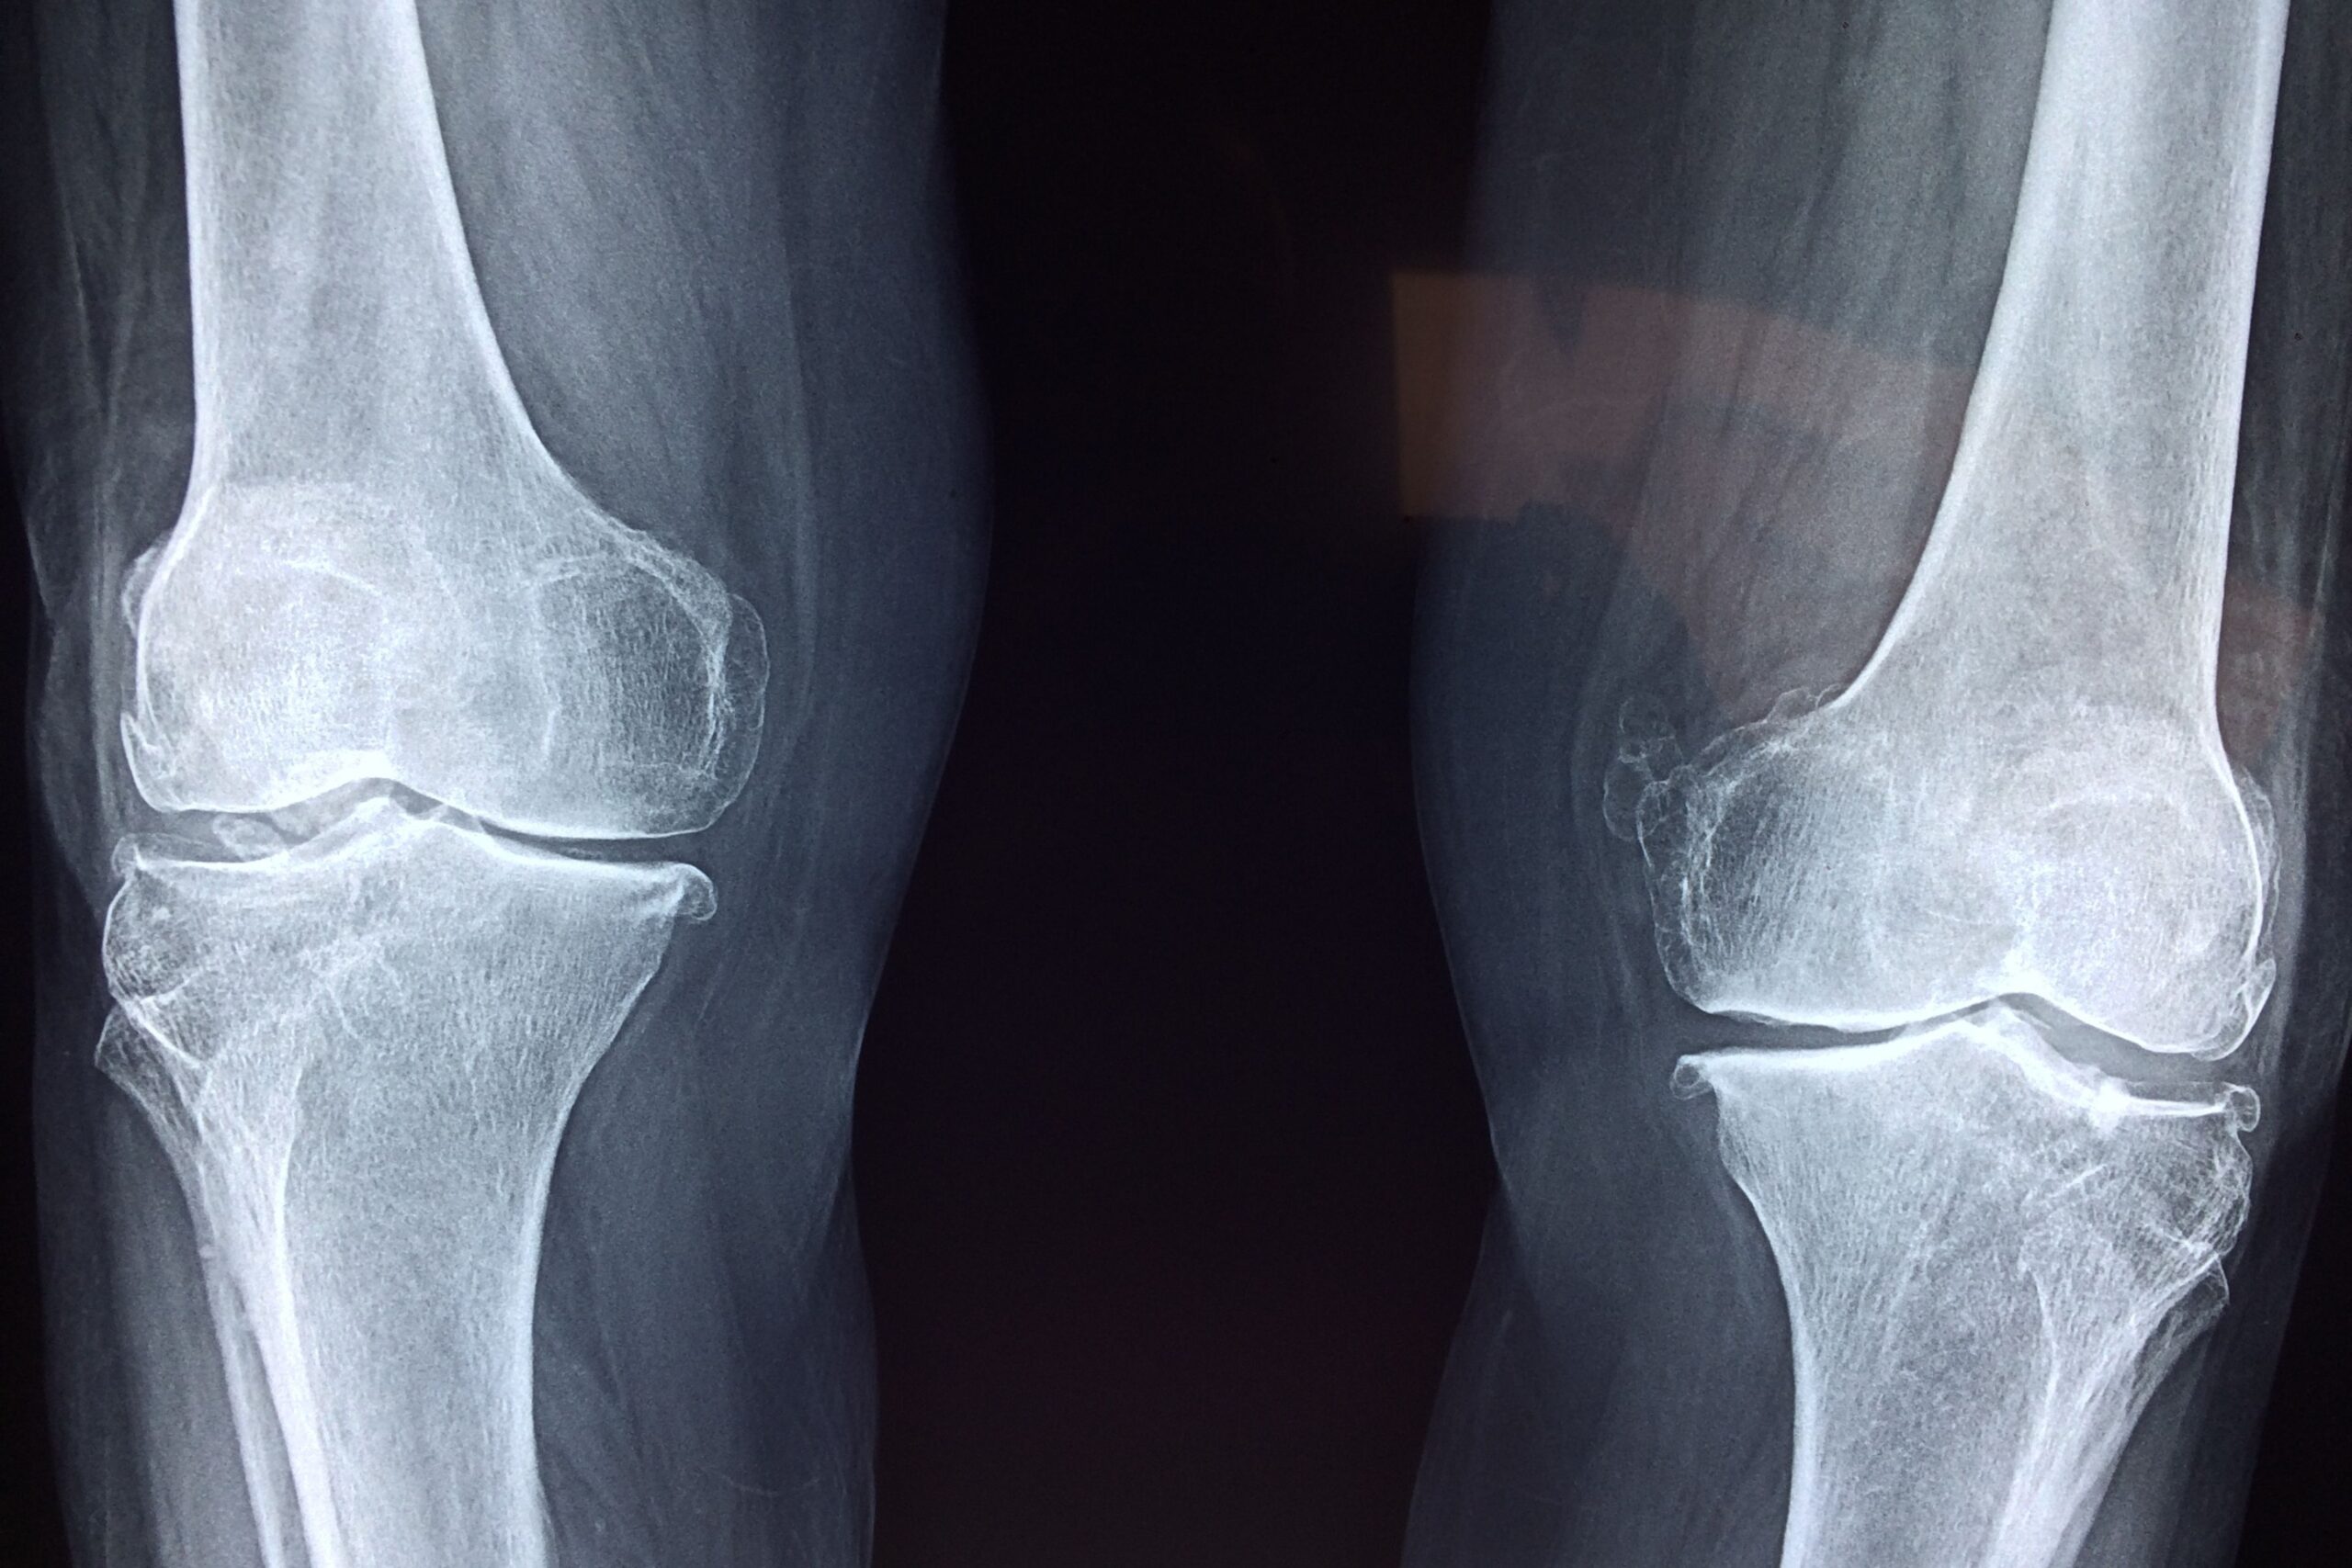

La ricerca, condotta presso l’Università di Birmingham, ha avuto l’obiettivo di valutare l’efficacia degli interventi di fisioterapia erogati tramite strumenti digitali rispetto alla fisioterapia tradizionale nei pazienti affetti da osteoartrosi del ginocchio. Gli autori hanno analizzato studi clinici randomizzati che confrontavano programmi riabilitativi digitali con interventi standard, considerando tre principali outcome clinici: dolore, funzione fisica e qualità della vita.

L’osteoartrosi del ginocchio rappresenta una delle principali cause di disabilità nella popolazione adulta e anziana. Le linee guida cliniche raccomandano esercizio terapeutico ed educazione del paziente come trattamenti di prima linea, prima di ricorrere a soluzioni farmacologiche o chirurgiche. In questo contesto, la fisioterapia digitale potrebbe diventare un importante strumento complementare anche nei percorsi multidisciplinari.